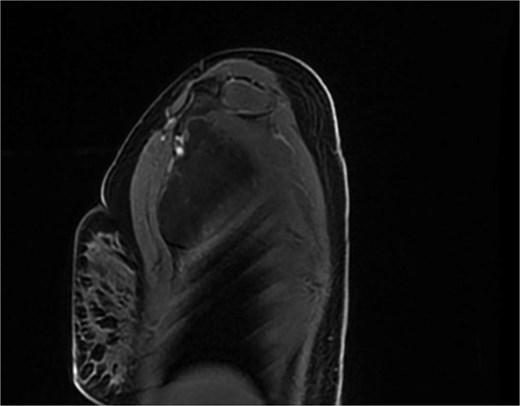

A 20-year-old previously healthy woman presented with a progressively enlarging, painless mass in the right chest wall extending into the axilla, associated with right arm heaviness, stiffness, and intermittent fatigue. She had a history of right cheek masses excised at ages 8 and 17, both histologically diagnosed as lymphangiomas. Examination revealed a large, soft, fluctuant, non-tender mass in the right axillary and lateral chest wall regions. MRI showed an 11.0 × 8.5 × 4.5 cm multiloculated cystic lesion with T2 hyperintensity and compression of the right axillary and subclavian veins (Figs 1 and 2). A diagnosis of recurrent cystic lymphangioma was established, and she underwent complete surgical excision with careful dissection to avoid neurovascular injury and management of lymphatic channels to reduce postoperative lymphocele formation. Postoperatively, her upper limb symptoms resolved, and she regained normal function. Given a recurrence risk of 10%–27% even with total excision, regular follow-up imaging was planned. This case underscores the need to consider lymphangiomas in adults with cystic masses, highlights the embryological explanation for ipsilateral recurrences along the cervicoaxillary pathway, and emphasizes the importance of MRI and computed tomography (CT) in diagnosis and surgical planning.

While cervical lymphangiomas dominate pediatric presentations, adult-onset axillary and chest wall lymphangiomas are exceptionally rare [2, 3]. Symptoms often manifest only after significant enlargement causes mass effect on neurovascular structures, as seen in our patient’s arm weakness and heaviness. MRI is the modality of choice, demonstrating characteristic T2 hyperintensity and thin septations; CT adds value in delineating relationships with critical neurovascular structures for surgical planning [3, 4].